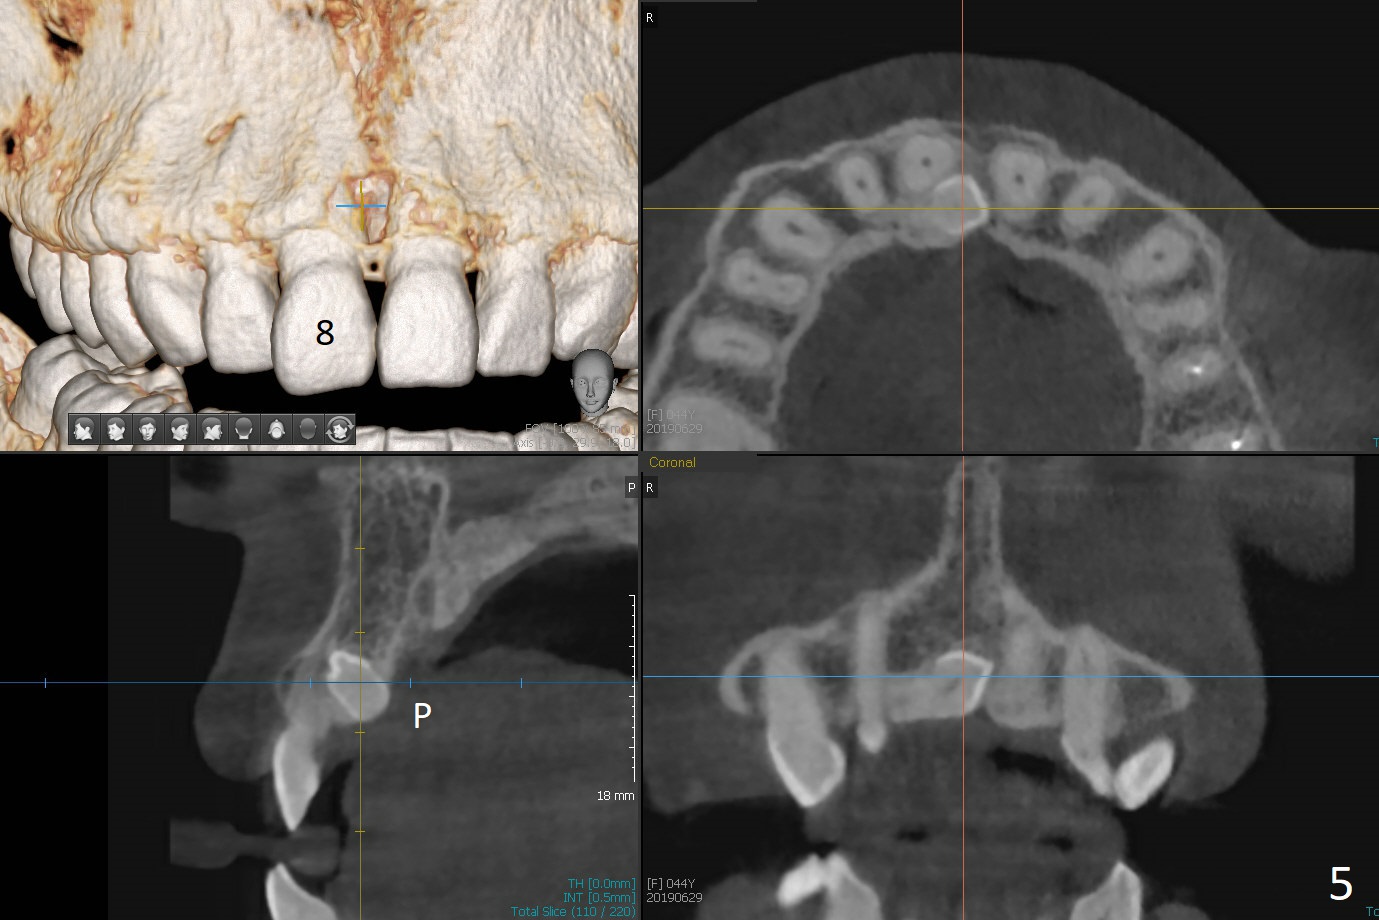

A 44-year-old woman used to have splinted crowns at #13 and 14 (Fig.1). Their dislodgement is due to residual roots at #13 and distal caries at #14 (Fig.2 ^). To avoid the distally curved apex of #12 and to have ideal trajectory of an IBS implant (Fig.4), osteotomy will be initiated in the distopalatal slope of the socket (Fig.3 arrowheads). The patient wants to correct the tooth #8 with rotation (Fig.5), which is due to a mesiodens (Fig.1,2 M). It will be accessed palatal (Fig.5 P). In fact there is percussion at #14 associated with MB2 (Fig.6 arrowheads) and PARL (*).